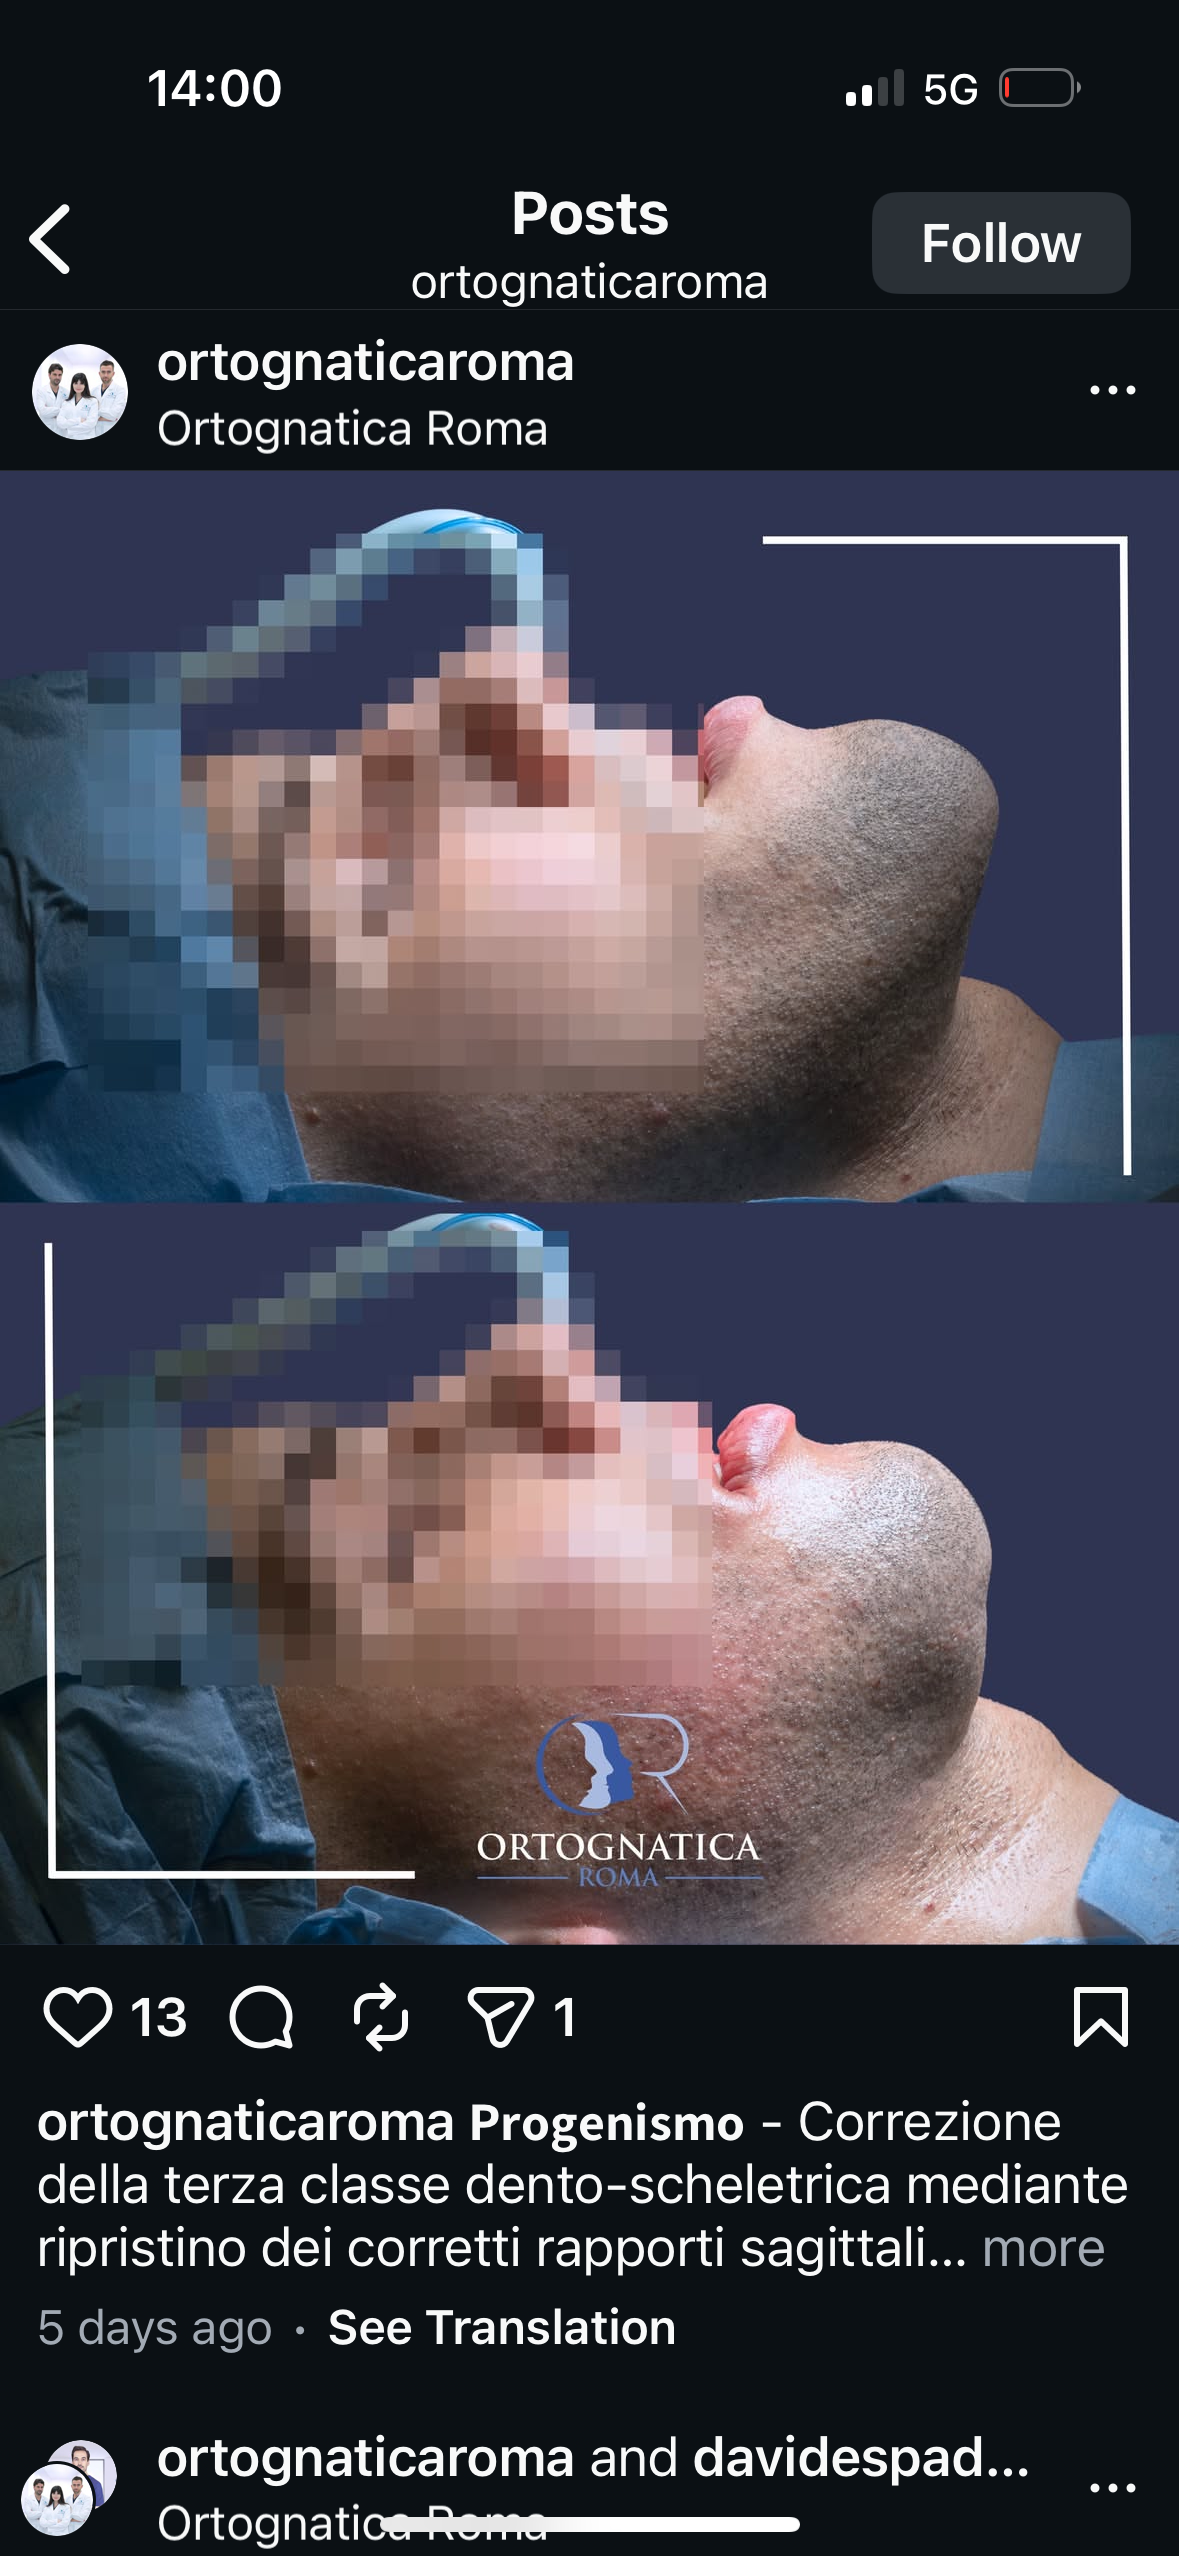

For your knowledge, I’ve seen the recent results of Ramieri, no one in here can say that his results are optimal, your extremly bias if you do. He can’t do a proper genioplasty because I don’t think he freaking knows how to use bonegrafts which explain all the irregularities in his patient from his recent revolutionary method, “stairway genioplasty”.